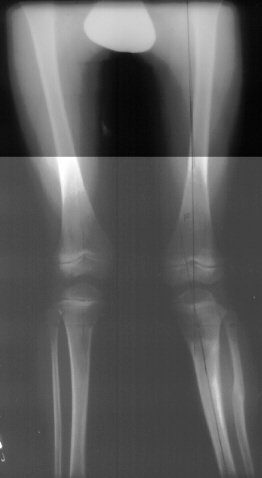

The history of this lesion is for rapid recovery of the valgus if significant growth is remaining. This child had an osteotomy, 3 Months post Surgery the mechanical axis on the left was 6 degrees. The x-ray at 9 months post surgery showed the mechanical axis on the left was 10 degrees.